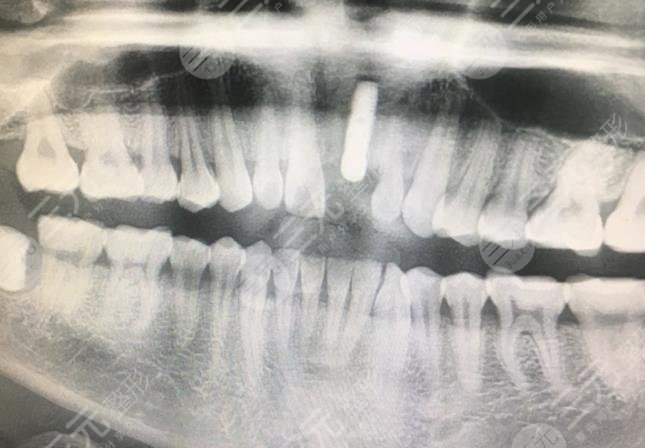

In daily life, some people are forced to implant teeth because of the lack of teeth, but many people do not know much about dental implants, and feel terrible, in fact, they are not, I share the whole process of doing dental implants, because of an accident that caused a front tooth to fall out, for various reasons, I have not repaired it, until I participated in the work, and suddenly felt that this tooth was too unfavorable to the overall image of the individual. I learned that it was related to this lost tooth.

So I had the idea that I must do a good job of this tooth, but considering that the price would be a little too expensive, so I didn't do it, and now I am promoted to supervisor in general employees, so I am slowly communicating a lot, and there are many people who deal with it every day, and my own image is really more critical, so I took out some money to do dental implants that I was reluctant to do before. At the suggestion of a friend, I rushed to Wuhan Dehan Stomatological Hospital to carry out dental implants.

The process of formal dental implant is a bit long, longer than the general dental surgery, it lasts for more than 2 months, because after the implant is implanted, you need to wait for it to grow before the follow-up operation, the important thing is the implant is followed, and then the abutment and crown are followed, the overall operation is still very smooth, and the result is relatively good.

(Click here!) Free online consultation price)After the surgery, I looked in the mirror and it was true, and the newly implanted tooth seemed to be slightly whiter than the other teeth, but it was not noticeable. Now it has been more than a month since the implantation of the tooth, and I went to the follow-up a few days ago, and the doctor said that it was very good, there was no problem, and I was very happy. I hope that my sharing can help some people who want to understand the whole process of dental implants.